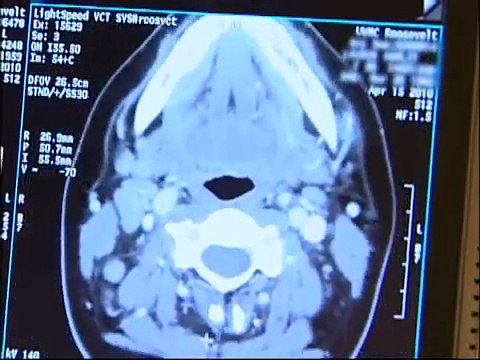

AIMMS LIBRARY VIDEO NO 22 CT SCAN COURSE CT Animation - Computed Tomography How to generate sinograms in a CT scanner